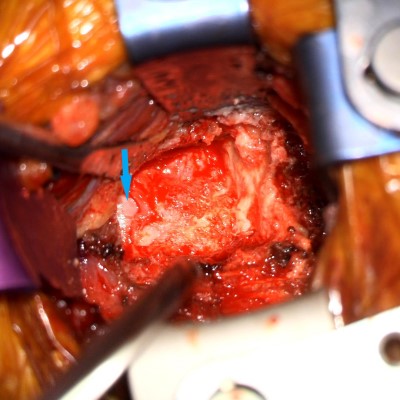

- Intra-op